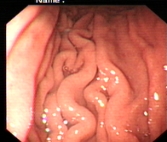

正常胃表现

内镜下表现:黏膜红白相间,以白色为主,黏膜皱襞变平或消失,部分黏膜血管显露,可伴有黏膜颗粒或结节状等表现。如伴有肠化生于电子染色窄带成像放大内镜(NBI ME)下发现胃粘膜上皮细胞表面的脑回样结构嵴部的纤细浅蓝色线样结构。病理活检可进一步确诊。